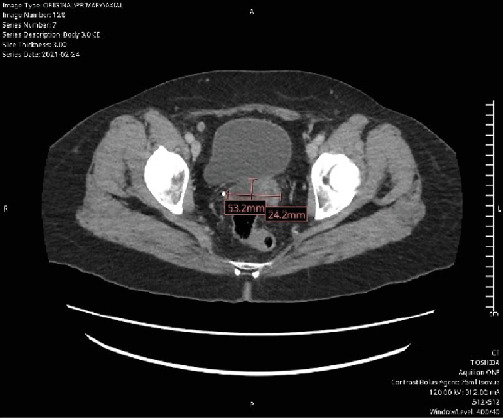

Background: Advanced stages of ovarian clear cell carcinoma have poorer prognoses than many other ovarian cancers. When standard treatments are ineffective, alternative options are needed. Case: A 56-year-old woman was diagnosed with ovarian clear cell carcinoma and treated with surgical management as well as carboplatin and paclitaxel. At recurrence, her disease progressed despite multiple chemotherapy regimens. A durable response was achieved first with alpelisib, chosen based on genomic testing. When progression occurred on this agent, a partial disease response was achieved with the combination of nivolumab and ipilimumab. Conclusion: The use of targeted therapies as well as the combination of nivolumab and ipilimumab is a promising option in advanced and recurrent cases of ovarian clear cell carcinoma.